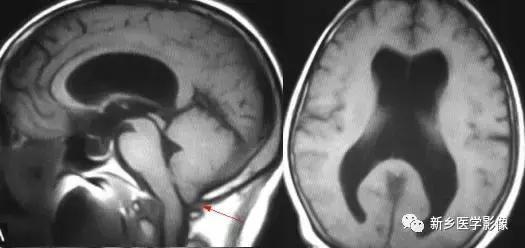

(1)前脑无裂畸形: (holoprosencephaly)是指一系列位于中线程度不同的畸形,累及大脑、面部、脑于和小脑.前脑未能够分开,呈不全性或完全性,端脑和间脑无法区分。根据脑及面部畸形程度将其分为无叶型、半叶型和单叶型。

无叶型前脑无裂畸形最严重.端脑半球间没有裂隙,呈马蹄形或新月形扩大的单脑室跨越中线,与背侧囊交通。丘脑互相融合,面部畸形从两眼距离过近到独眼畸形.往往死于胎儿或新生儿期。

半叶型前脑无裂畸形在前脑可见部分裂隙. 形成不同发育程度的大脑纵裂及大脑镰。两侧大脑半球在前部未完全分开,但枕叶和 双侧侧脑室体部分离,丘脑分开不完全。三脑室和海马发育不全,胼胝体仅可见到压部,而其他部分缺如.额叶和基底节前部分辨不清。临床表现有两眼距离过近.及唇裂、腭裂等面部畸形,侧脑室呈单一性.且明显扩大。

单叶型前脑无裂畸形与正常发育脑仅有些很小的区别.如透明隔缺如或双侧额叶不完全分开。